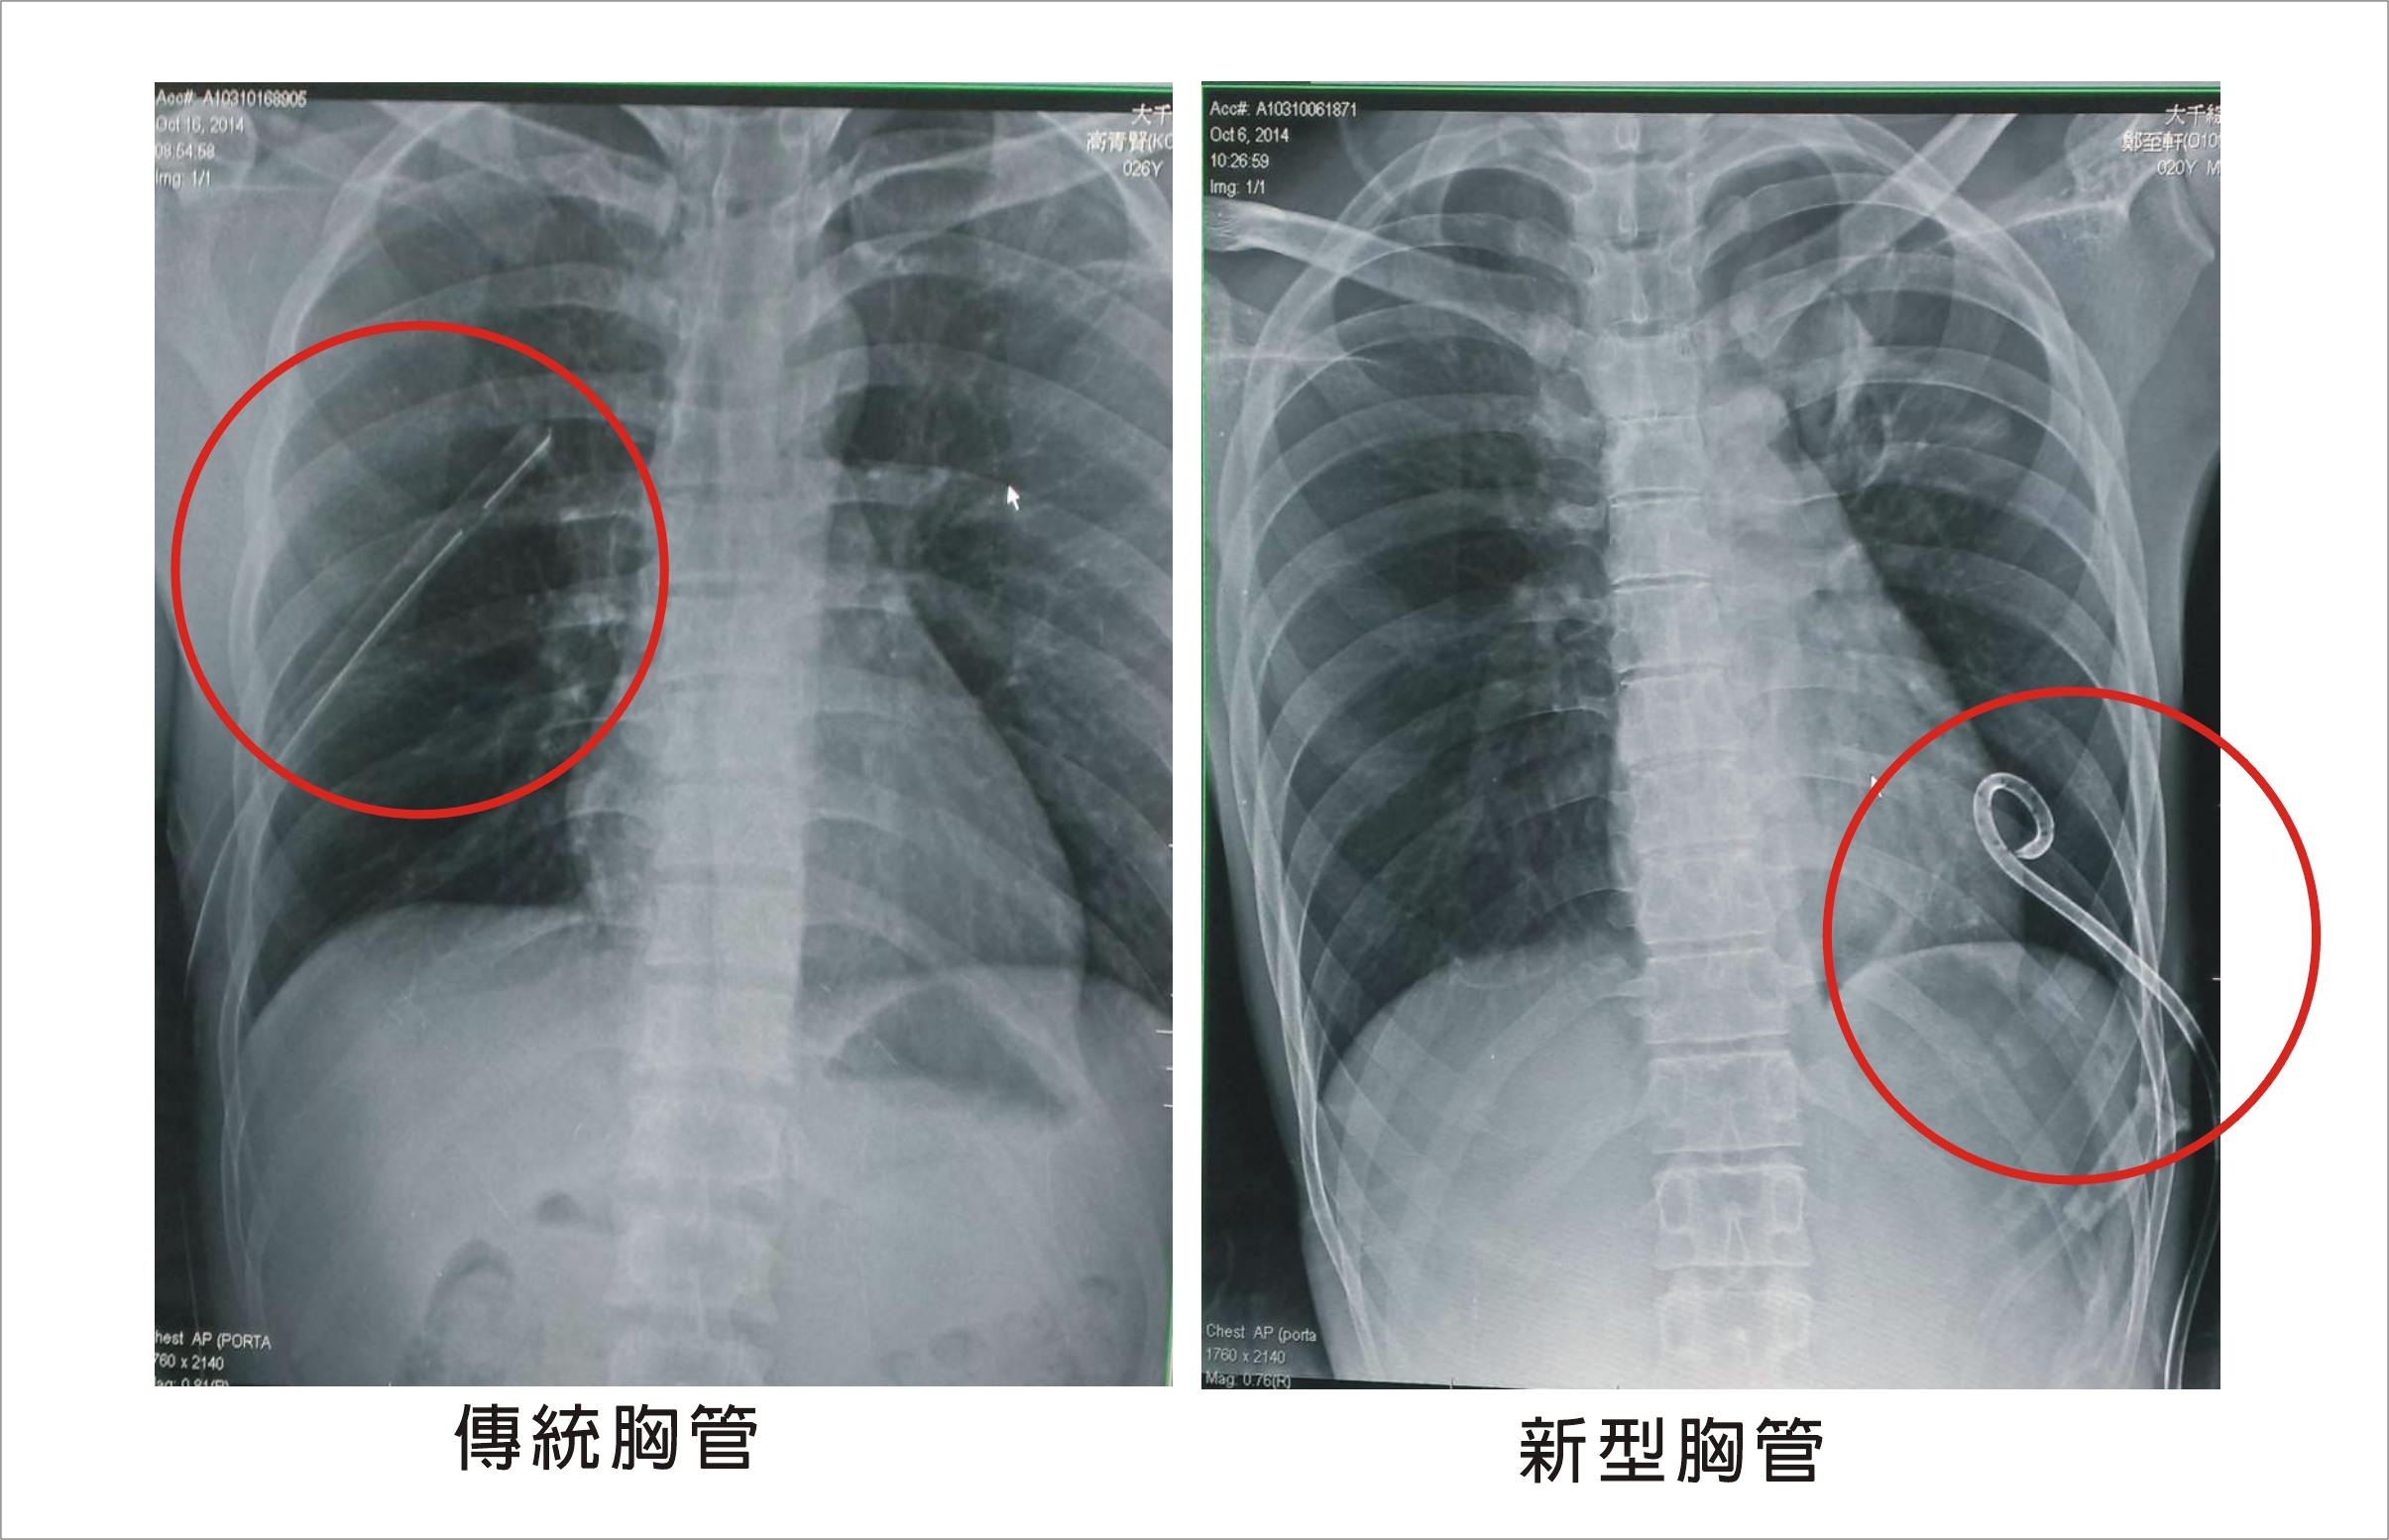

【大成報記者劉鳳瑩/苗栗報導】一位20歲的男子兩天前打完籃球後開始感到胸痛、呼吸不順,緊急送醫照胸部X光後發現為自發性氣胸,醫師以微創胸管手術將氣體排出,較傳統手術疼痛感輕,傷口也不需再縫合,病人術後也可自由活動不受限制。

然而,傳統型的胸管需要以手術置放,傷口約1-1.5公分,手術後病人因為需要配帶氣胸引流瓶,因此只能臥床休息,活動受限。陳主任建議目前已引進微創胸管手術,傷口只有0.2-0.3公分,因此病人手術後疼痛感較輕,傷口也不需再縫合,可以自由活動不受限制。